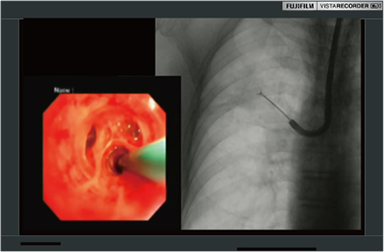

録画範囲のトリミングにより、内視鏡画像も透視画像も大きくPinP録画。特に内視鏡と透視を1:1で録画するときに役立ちます。

TBLB